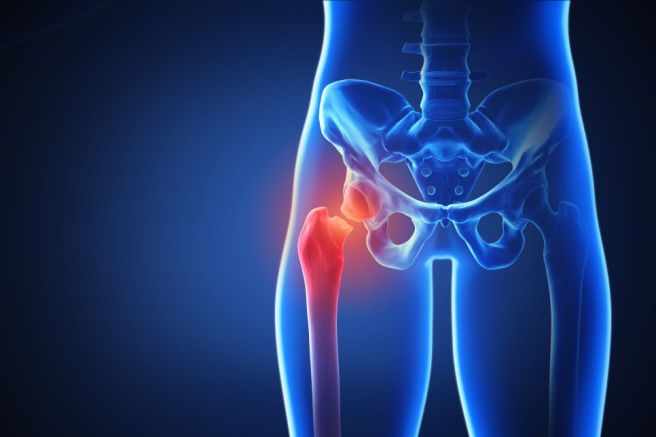

고관절 골절은 주로 대퇴경부나 대전자 부위에 발생하며, 뼈의 구조적 손상에 따라 다양한 증상이 나타납니다.

가장 흔한 증상은 극심한 통증으로 보통 넘어지거나 외상을 입은 직후 고관절 부위에 날카롭고 깊은 통증이 발생합니다. 통증은 움직이거나 다리를 들어올리려 할 때 더욱 심해지며, 골절이 심한 경우에는 누워 있는 상태에서도 통증이 지속됩니다.

골절이 발생한 쪽 다리는 반대쪽보다 짧아 보이거나 바깥쪽으로 돌아가 있는 경우가 많고, 특히 대퇴경부 골절에서는 다리의 외회전 변형이 뚜렷하게 나타납니다.

스스로 걷거나 일어설 수 없는 상태가 흔하며, 다리에 힘이 들어가지 않아 지탱이 어려워집니다. 또한 관절 주변이 붓거나 멍이 들 수 있으며, 움직일 때 뼈가 부러지는 듯한 마찰음이 들리기도 합니다.